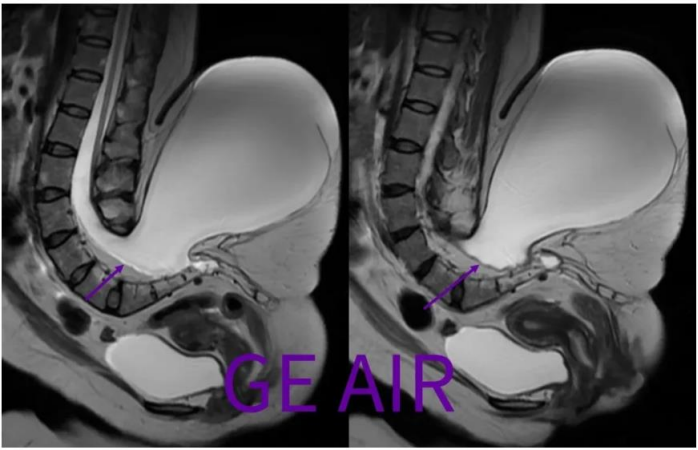

北京的专家主要想看这个囊肿的结构,以及与周围组织的关系,申请磁共振平扫。兄弟单位磁共振室由于患者无法平躺而婉拒,现来我院试试最新的3T磁共振。 患者家属还带了一些图片(可能引起不适):

回顾性翻看矢状面T2和T2 fs,由于椎管内脂肪(红箭)和脑脊液交界,化学位移现象很重,所以干扰了囊性包膜的显示。